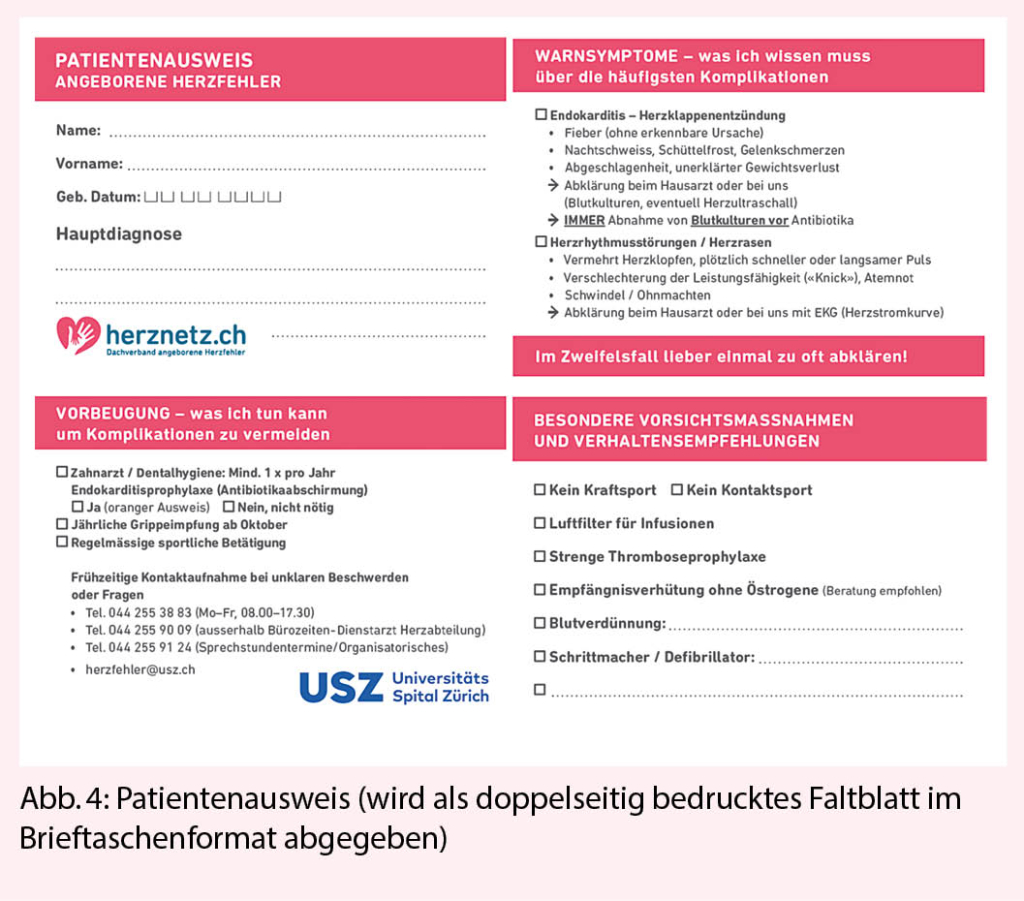

Wie oben erwähnt kommt der Patientenedukation grosse Bedeutung zu. Über den Dachverband www.herznetz.ch wurden über die letzten Jahre verschiedene Edukationstools entwickelt, die zur Unterstützung eingesetzt werden können. Im Alltag als sehr hilfreich und effektiv hat sich ein kleines Faltblatt erwiesen, das die wichtigsten Komplikationen und die einschlägigen Vorsichtsmassnahmen zusammenfasst. Wir verwenden dies als Unterstützung der mündlichen Patienten-Edukation (Abb. 4). Dieses Faltblatt steht in deutscher, englischer und italienischer Sprache zur Verfügung (www.herznetz.ch/service/mini-kg).